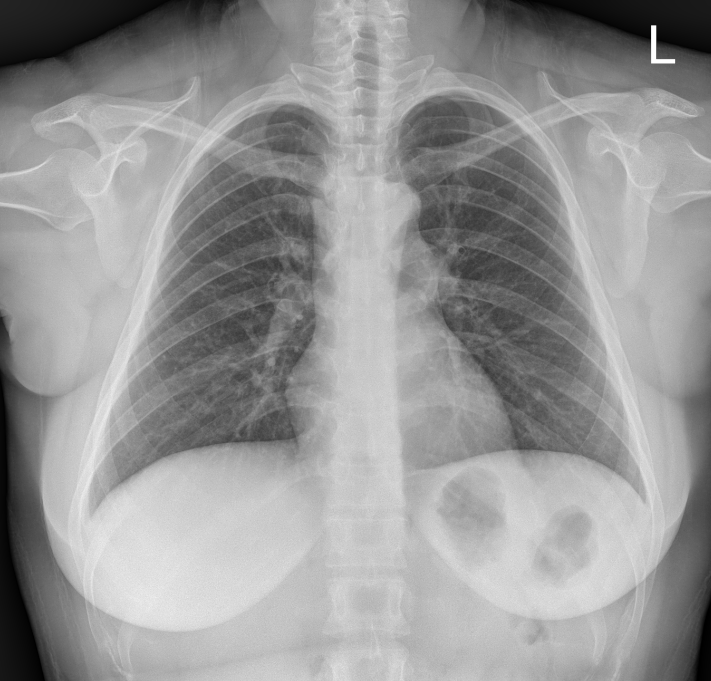

F/34

°Ç°­°ËÁø»ó ½ÃÇàÇÑ Chest PA »ó mediastinal widening ¼Ò°ßÀ¸·Î further evaluation À§ÇØ ³»¿øÇÔ.

Áõ»óÈ£¼Ò ¾øÀ¸¸ç ½Åü°ËÁø»ó ƯÀÌ¼Ò°ß ¾øÀ½.